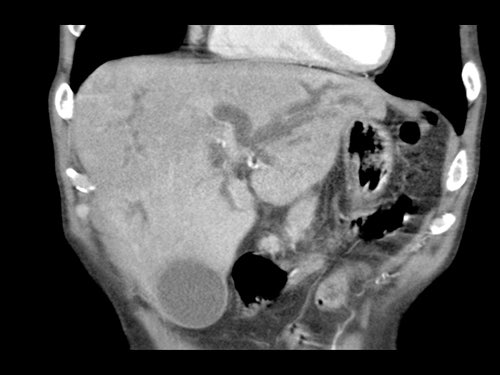

Tái tạo mặt phẳng coronal cho thấy một khối u lớn xuất phát từ cổ tụy với kiểu phát triển xâm lấn (hình A và B).

Có hiện tượng bao quanh động mạch thân tạng 360º (mũi tên trong A).

CT axial MIP tại mức động mạch thân tạng cho thấy hẹp động mạch gan chung bị bao quanh (mũi tên), rất nghi ngờ xâm lấn.